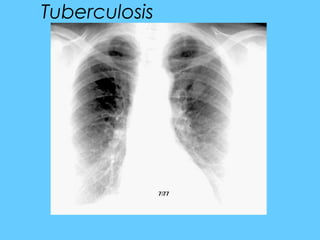

Tuberculosis